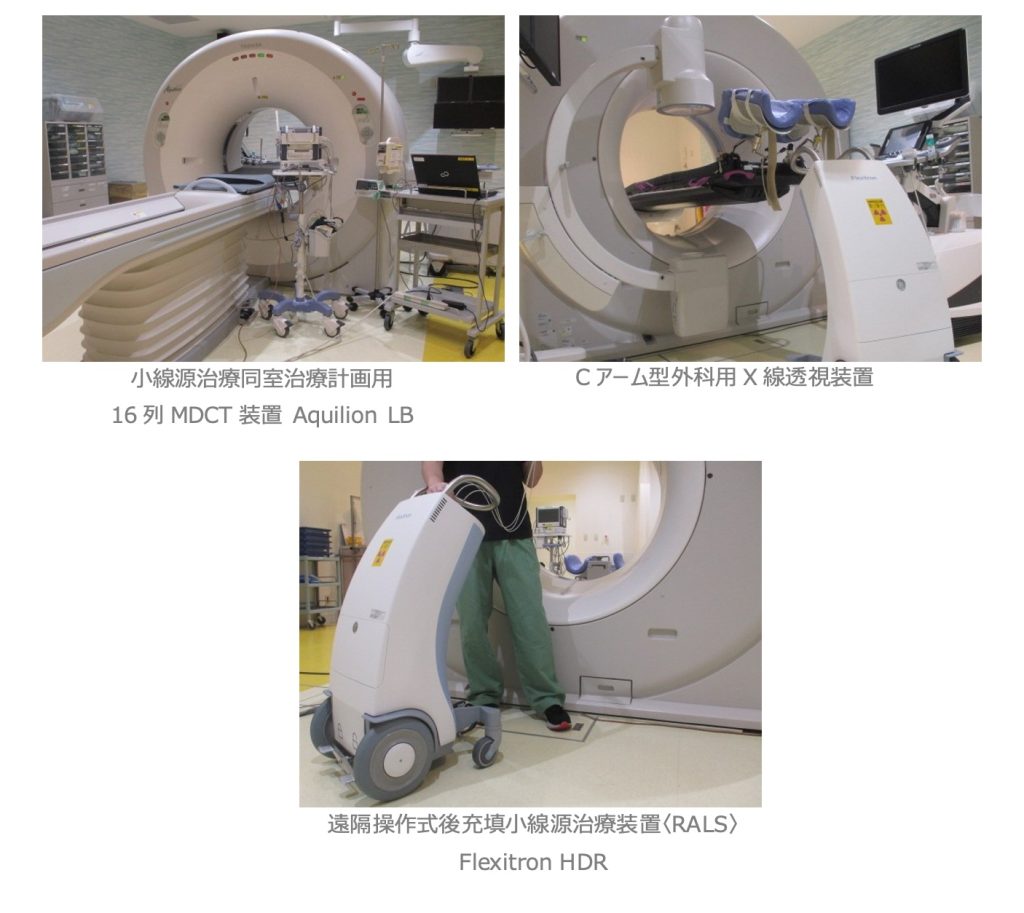

密封小線源治療は、体腔内に専用の器具を挿入したり、体に針を刺すことで、腫瘍の極近傍もしくは腫瘍内部まで密封小線源を移動させて、腫瘍に対して高い線量で放射線を照射しつつ、周囲の正常組織における放射線量を低く抑えることが可能な、体の中から放射線を照射する治療法です。当センターでは、照射に必要な処置から治療計画用CT撮影まで、全て同室で移動なく行える設備と体制を整えております。

●MR画像誘導放射線治療システム MRIdian Linac

《メリディアン リニアック:VIEWRAY社》

6MV-X線リニアック装置と0.35テスラの低磁場MR装置を融合させたシステムで、MR画像を位置照合に使用して正確に照射する“MR画像誘導放射線治療“を行う事が出来ます。更に、腫瘍や周囲臓器を随時観察する事ができ、状況に応じて治療計画の見直しを行い、最適な照射に切り替える”On-Line Adaptive RT”が可能です。また、照射中にMR画像を撮像しながら呼吸により移動する腫瘍に対して、正確に放射線を照射する“Real Time Gating“の機能が備わっています。当センターに2022年度導入された装置です。